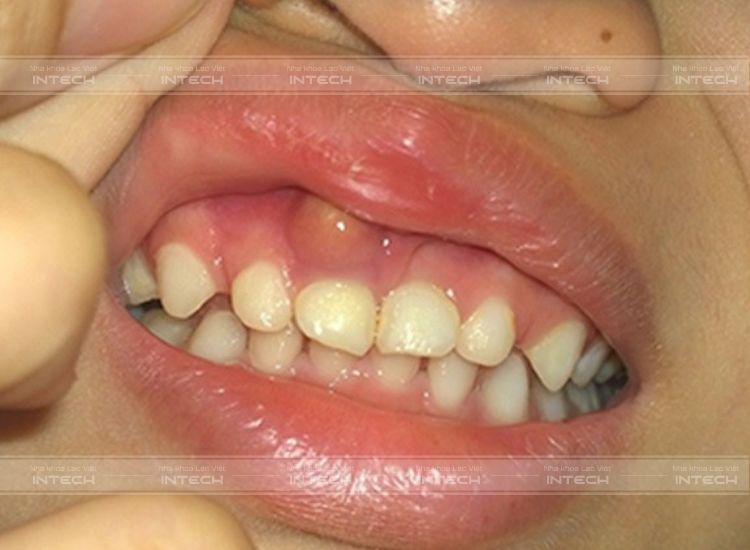

Hình thành túi mủ trên nướu răng

Đây là bệnh lý răng miệng xảy ra trong trường hợp nướu bị nhiễm trùng, gây hôi miệng, sưng và đau nhức. Các tế bào miễn dịch trong cơ thể sẽ tập trung tại vị trí lợi bị viêm để loại bỏ  các vi khuẩn gây hại. Do đó, đây là thời điểm ổ mủ hình thành nên bởi tập hợp của các xác của tế bào và vi khuẩn còn sót lại, từ đó gây ra tình trạng nhiễm trùng và sưng tấy các mô ở chân răng.

Nướu sưng đỏ

Nướu sẽ trở nên sưng to và đỏ hơn bình thường tại vị trí xung quanh vị trí bọc mủ. Khi bệnh nhân dùng tay để ấn vào các vị trí này đôi khi sẽ thấy có dịch có mùi hôi tiết ra hoặc có thể là máu.